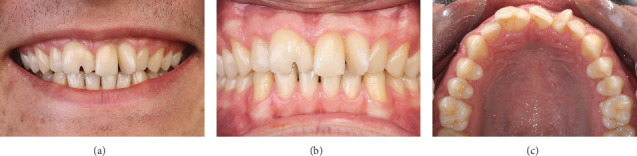

这个临床报告描述了一个18岁的男性患者,有新生和多余的上颌门牙导致前牙拥挤和审美问题。在这种情况下,保守的跨学科方法包括数字分析,多牙拔牙,正畸空间管理和陶瓷贴面。通过这些保守的多学科治疗和数字分析,保持了生牙的活力,美观,功能和患者自尊得到了显着改善。

This clinical report describes an 18-year-old male patient that had geminated and supernumerary maxillary incisor teeth causing anterior dental crowding and esthetic problems. In this case, a conservative interdisciplinary approach that included digital analysis, supernumerary tooth extraction, orthodontic space management, and ceramic veneers was done. With these conservative multidisciplinary treatments and digital analysis, the vitality of the geminated tooth was maintained, and the esthetic, function, and patient self-esteem were improved significantly.